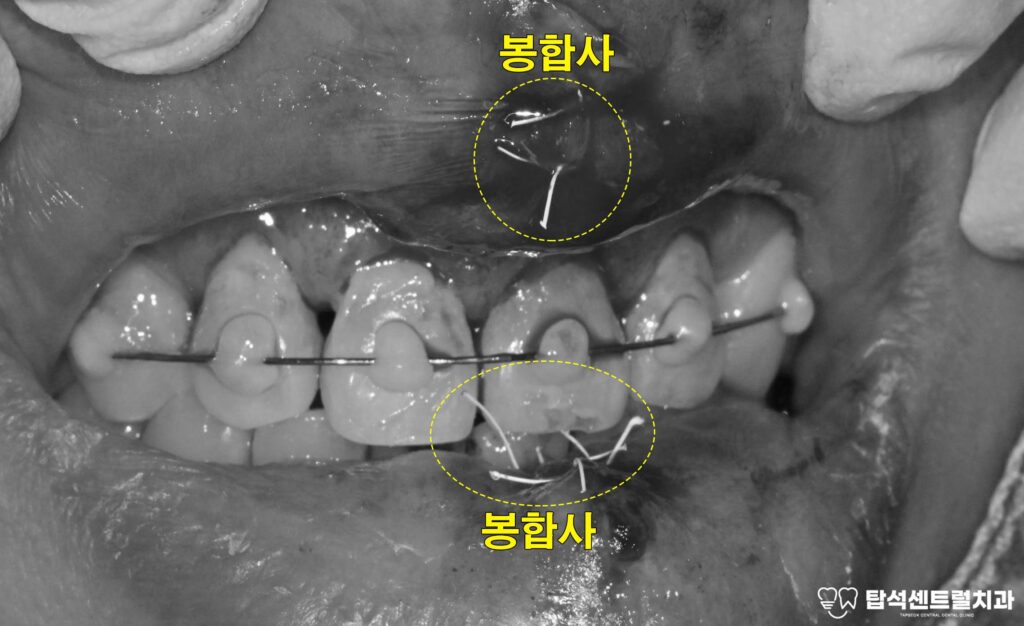

용현동 치과 에서 보여드리는

케이스의 경우에는 앞니부터 송곳니까지

이어지는 치아 (#13=12=11=21=22=23) 6개에

와이어를 부착하였습니다.

입술이 찢어진 경우에는

연조직 봉합을 시행합니다.

이때 특수 소재의 봉합사를 사용하여,

상처 부위를 정교하게 꿰매게 됩니다.

이 시술을 시행할 때는 전치부와

주변 부위를 와이어로 연결합니다.

예를 들어 윗쪽 송곳니부터

반대편 송곳니까지 총 6개를

함께 묶을 수 있습니다.